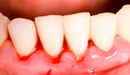

Travmaların Etkileri konusuna gelince, doğum sırasında yaşanan travmaların etkileri üzerine daha fazla bilgi sahibi olmak, bu tür kanamaların daha iyi yönetilmesine yardımcı olabilir. Özellikle doğum sırasında meydana gelen yırtıklar veya diğer komplikasyonlar, doğum sonrası kanama riskini artırabilir. Bu nedenle, doğum öncesinde ve sırasında doktorların dikkatli bir değerlendirme yapması, önleyici tedbirler alması kritik öneme sahiptir.